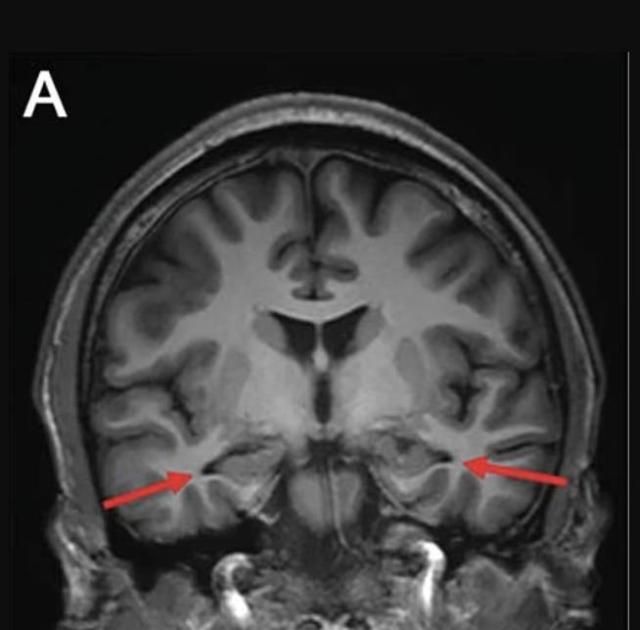

وأوضحوا: «أظهرت فحوص الدماغ انكماشاً في الحصين، وهو مركز أساسي لتكوين الذاكرة، كما كشف تحليل السائل النخاعي عن مستويات غير طبيعية من بروتينات الأميلويد والتاو المرتبطين بمرض الزهايمر».